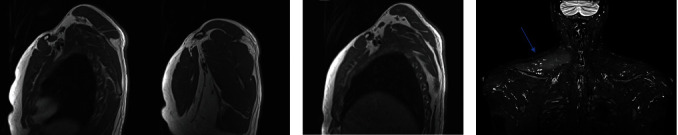

Abstract Image